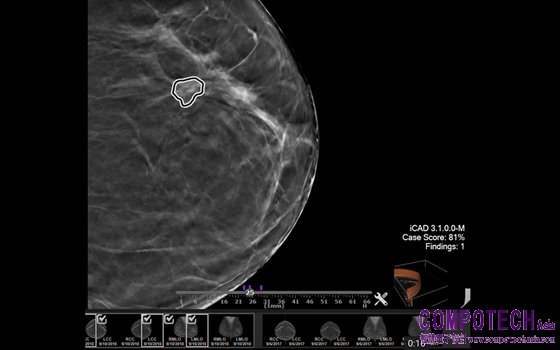

圖一_透過 NVIDIA AI Enterprise,醫院的 IT 管理人員可以同時運行 AI 應用程式與醫院的核心應用程式,如用於乳房攝影檢查的 iCAD Profound AI 軟體

放射科醫師使用 iCAD 的創新 ProFound AI 軟體來協助讀取乳房攝影影像。這些AI 解決方案有助於早期發現癌症、對乳房密度進行分類,並根據每位女性的乳房攝影結果,準確評估個人短期罹患乳癌的風險。利用 VMware vSphere 運行先進的作業負載對 iCAD 的醫療客戶來說非常重要,他們可以輕鬆地將其資料密集型應用程式納入任何醫院的基礎設施中。